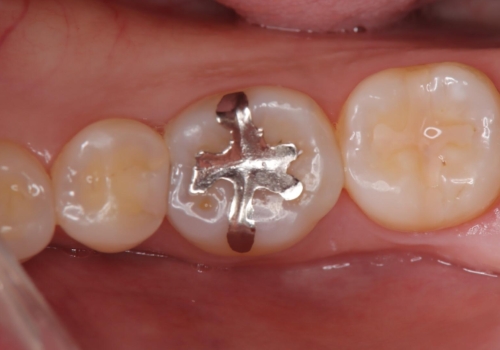

- 虫歯が複数個所あり、来院回数を抑えて治療をしたいという患者様でした。当院では光学スキャナ・ミリングマシンを設置しておりますので、1日でセラミック修復治療を完了させました。術後も良好な経過をたどっています。

メタル修復物の場合X線を通さない性質があり、レントゲン写真を撮るとメタルの部分が真っ白に写ってしまうため、詰め物の下の虫歯が分かりにくくなってしまうというデメリットがあります。これに対し、今回の即日セラミック修復に使用したMarkⅡという材料は、レントゲン写真からもわかる通り歯の一番外側の部分(エナメル質)と同程度のX線透過性を持ちます。そのため装着後も定期的なメンテナンスにより虫歯の再発を早期に発見できるメリットがあります。